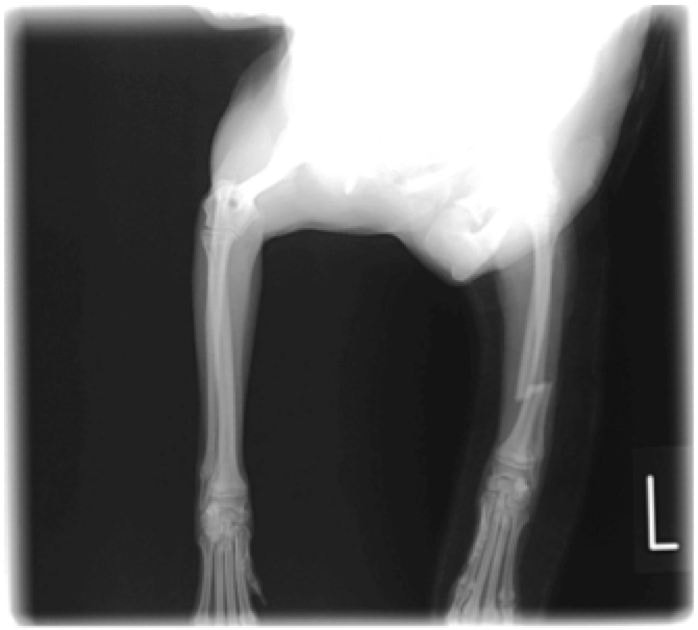

ペルシャ猫 11ヶ月齢 雄

他院にて左大腿骨遠位の成長板骨折(salter-harrisⅠ型)が認められており、治療相談を目的として来院。当院にて、キルシュナーワイヤーを用いたピンニングにより骨折部位の整復を行いました。術後の経過は良好で、現在も経過観察中です。

術後レントゲン